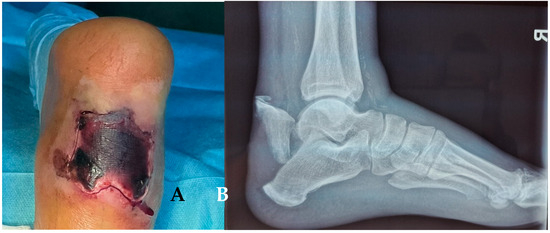

Background: Covering the defects around the calcaneus is still a largely debatable subject. In the classical view, the defects at the level of the foot can be treated only by a free flap. In a modern approach, it has been observed that for small or m...